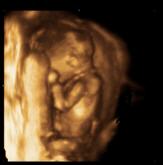

Aufnahmen aus der 16. Schwangerschaftswoche. Die Scheitel-Steiß-Länge beträgt ca. 9,4cm. |